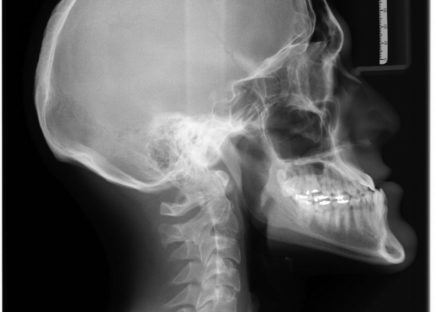

Røntgenundersøgelse: Diagnostiske billeddannelser

En røntgenundersøgelse er et diagnostisk værktøj, der har revolutioneret måden, vi ser ind i kroppen uden at udføre kirurgiske indgreb. Når man taler om røntgenstråler, forestiller mange sig ...